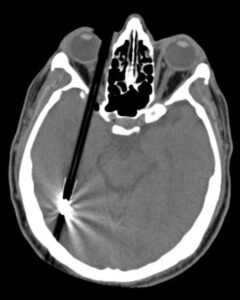

3D-CT reconstruction ofa-child-who-fell-on-a-writing-pen-The-pen-entered-the-right

A CT scan will also show whether there are associated fractures and if the object has penetrated into any deeper structures, such as the brain. If the foreign body is wooden it may not be seen on X-ray or CT, and an MRI scan may be necessary. Emergency Trauma services in Mumbai are available at Wavikar Eye Hospital.

3D-CT reconstruction of a child who fell on a writing pen. The pen entered the right